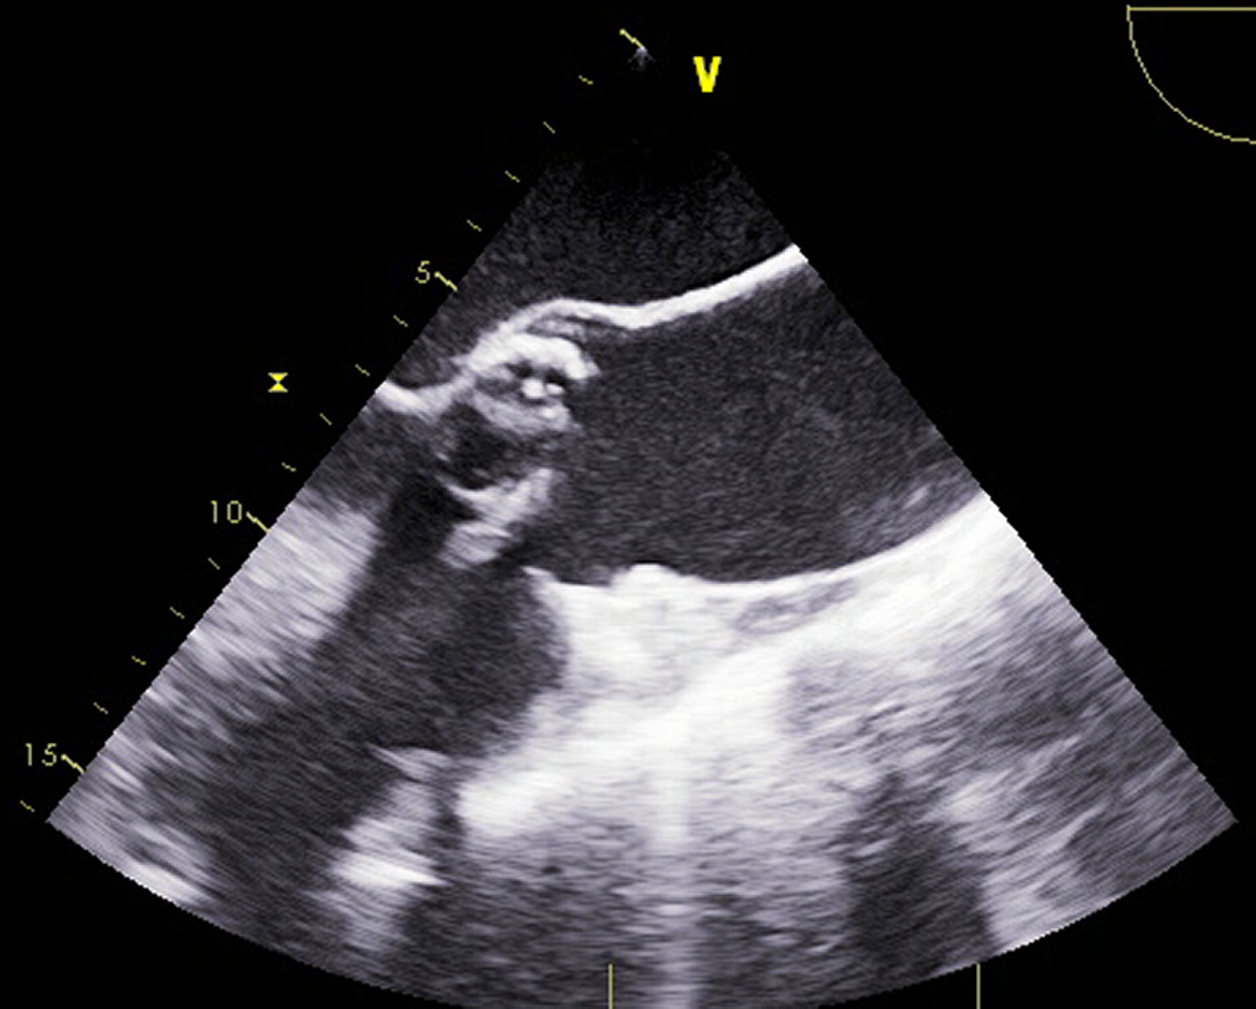

Abstract Body (Do not enter title and authors here): Introduction: Patients with a bicuspid aortic valve (BAV) often have an associated aortopathy, increasing their risk of aortic dissection. Currently, there is no proven therapy to stabilize the growth of BAV aortopathy. This study aimed to assess the effect of cardioprotective medications, specifically renin-angiotensin-aldosterone system inhibitors (RAASi), on the progression of aortic dilation in adult BAV patients.

Methods: A retrospective cohort study was conducted including adult patients with BAV followed at our center between 1996-2020. All patients had echocardiography imaging with at least 5 years of follow-up. The cohort was divided based on the chronic use of RAASi, as determined by pharmacy check-out data. The primary endpoint was defined as either the progression of ascending aortic diameter ≥ 4.5 cm or surgery for ascending aortic replacement.